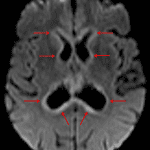

- Thick diffuse restricted diffusion along the margins of the ventricular system with corresponding linear and nodular enhancement

- Enhancement also extends along the hypothalamus and pituitary stalk

- Subependymal T2/FLAIR signal hyperintensity also involving the inferior aspects of the lentiform nuclei, the hypothalamus, and the optic tracts

- Mild prominence of the ventricular system, possibly representing communicating hydrocephalus

Secondary CNS lymphoma